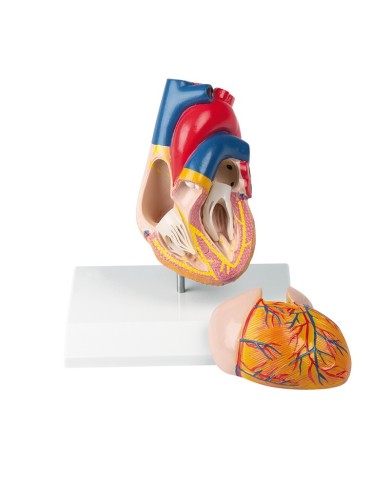

Modello di cuore di alta qualità scomponibile in 5 parti

Modello di cuore di alta qualità scomponibile in 5 parti

La parete anteriore del cuore è staccabile per poter vedere i ventricoli.

Questo modello dettagliato mostra, oltre alle strutture anatomiche del cuore, anche una parte del diaframma (base)